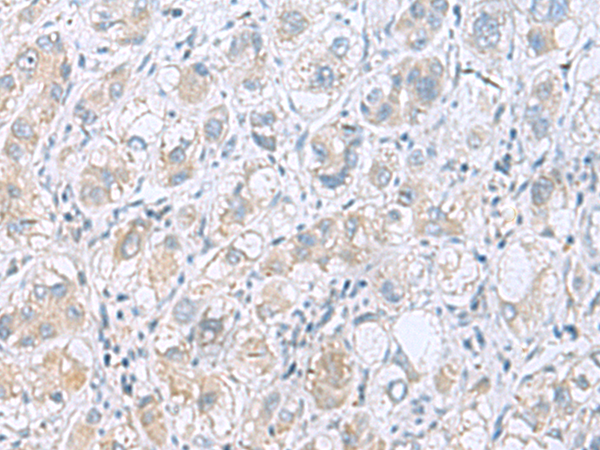

分类: 科研抗体货号: P10215别名: MAGED3; MAGE-d3应用: IHC反应种属: Human